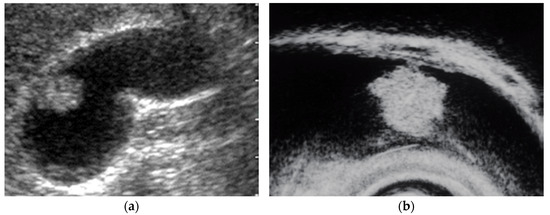

| Adenomyomatosis | no fixed size | sessile | oval | relatively smooth or granular | multiple anechoic aresa comet tail artifact |

| Adenomyomatosis | focal or diffuse | smooth | multiple anechoic areas comet tail artifact | preserved |